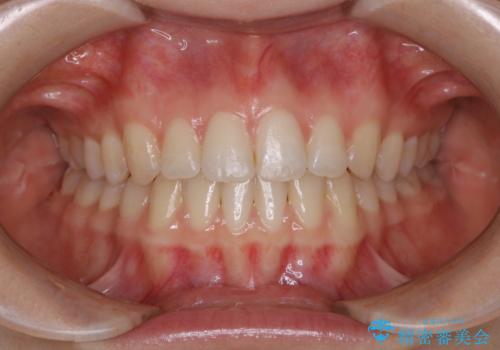

- 上下前歯のがたつきが気になるとご相談にいらした方です。

一見前歯のがたつきだけ改善させれば良い様に見えますが、このがたつきの原因は奥歯の嚙み合わせのズレからくるものであったため、インビザラインFULLで噛み合わせの改善から行っていきました。前歯の角度も改善されたために頑張って唇を閉じる必要がなくなり、横顔のシルエットも綺麗になりました。

前歯のがたつきだけを治そうとした場合、噛み合わせは二の次なってしまう事が多く、せっかく綺麗になった歯並びも後戻りしやすくなります。奥歯の噛み合わせからしっかり機能させることで、長期間にわたって綺麗な歯並びを保ちやすくなります。

インビザライン20時間以上正しく装着していただいたおかげもあり、短期間で治療することが出来ました。